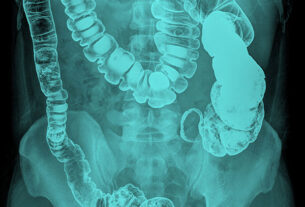

Imaging techniques remain foundational in cancer detection, with X-rays, CT scans, MRI, PET scans, and ultrasound widely used to evaluate tumour size, location, and metastasis.

Endoscopy provides direct visualization of organs using high-resolution cameras, aiding in detection and biopsy within the digestive and respiratory systems.

Screening programs such as mammography, Pap smears, and colonoscopy play a vital role in detecting cancer before symptoms appear, significantly improving survival outcomes.